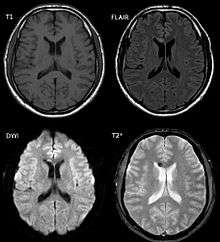

Diffuse axonal injury after a motorcycle accident. MRI after 3 days: on T1-weighted images the injury is barely visible. On the FLAIR, DWI and T2* weighted images a small bleed is appreciated.

DAI is difficult to detect since it does not show up well on CT scans or with other macroscopic imaging techniques, though it shows up microscopically.[2] However, there are characteristics typical of DAI that may or may not show up on a CT scan. Diffuse injury has more microscopic injury than macroscopic injury and is difficult to detect with CT and MRI, but its presence can be inferred when small bleeds are visible in the corpus callosum or the cerebral cortex.[21] MRI is more useful than CT for detecting characteristics of diffuse axonal injury in the subacute and chronic time frames.[22] Newer studies such as Diffusion Tensor Imaging are able to demonstrate the degree of white matter fiber tract injury even when the standard MRI is negative. Since axonal damage in DAI is largely a result of secondary biochemical cascades, it has a delayed onset, so a person with DAI who initially appears well may deteriorate later. Thus injury is frequently more severe than is realized, and medical professionals should suspect DAI in any patients whose CT scans appear normal but who have symptoms like unconsciousness.[2]

MRI is more sensitive than CT scans, but MRI may also miss DAI, because it identifies the injury using signs of edema, which may not be present.[20]